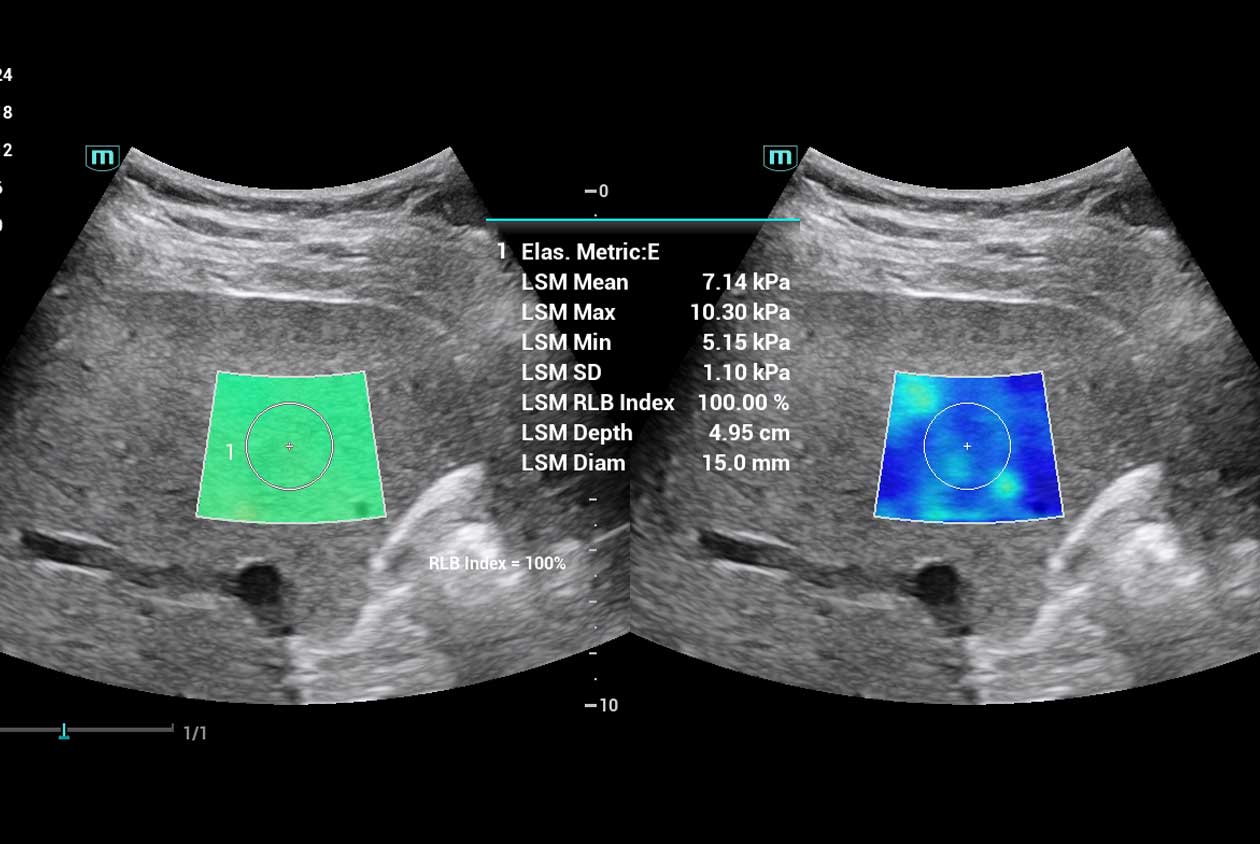

Clinical Images